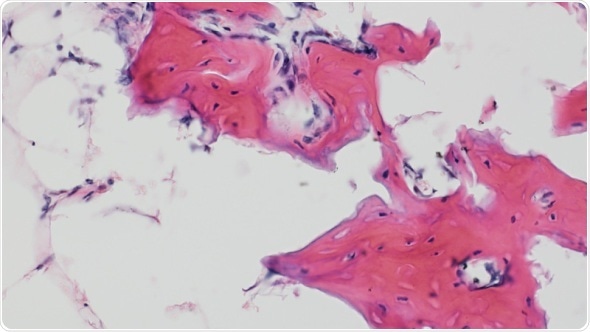

Bone regenerates when two human cell populations (pericytes and adventitial cells) are mixed and implanted in a skull bone defect in immunocompromised mice. Credit: Yiyun Wang, research fellow at the Dept of Surgical Pathology, The Johns Hopkins University School of Medicine

The study found that one of these perivascular stem cell types, pericytes, induces growth of new blood vessels, while another type, adventicytes, induces the formation of bone cells called osteoblasts. In laboratory tests, researchers found that the two types of cells did a better job promoting bone repair in mice with skull defects when they were used together than when either type was used alone. A description of the work was published online Jan. 7 in the journal NPJ Regenerative Medicine.

James and colleagues isolated pericytes and adventicytes from human liposuction specimens. To determine the functions of each cell type, they applied pericytes and adventicytes in equal numbers alone and in combination with nonhealing skull defects in mice. Then they used microcomputed tomography imaging (used for high-resolution assessment of bones and soft tissue) eight weeks later to study the amount of bone repair. Bone formation was just patchy in the mice given either one of the cell types, but was much more robust in the mice that received both cell types as a combination therapy.